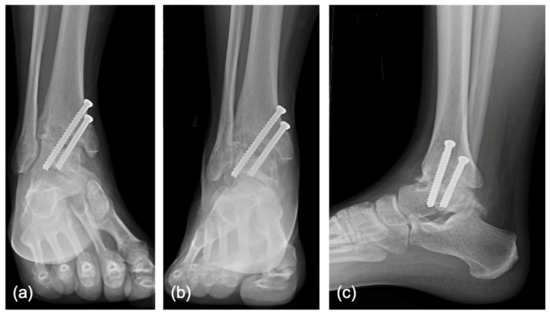

2.2. Surgical Technique